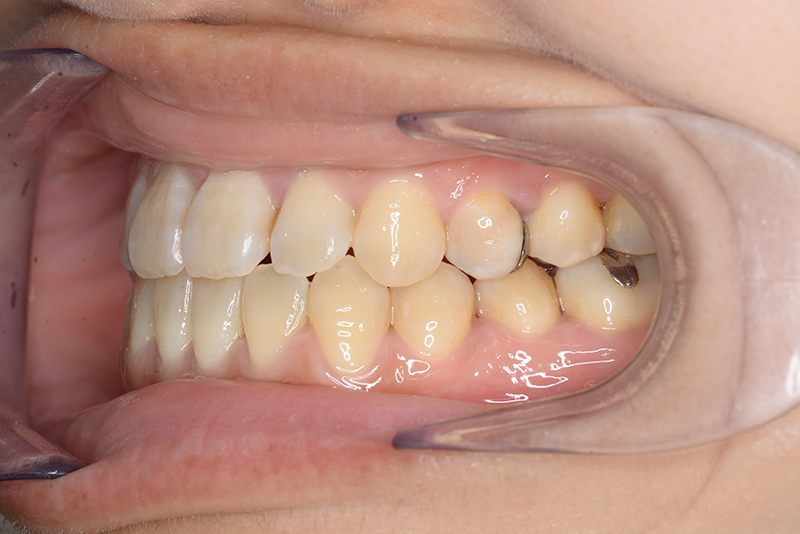

初診時

FP・IOP

主訴 受け口 診断名 アングルⅢ級反対咬合症例

初診時年齢 31歳6ヵ月 性別 動的治療期間 15ヵ月

口腔内所見 臼歯関係はⅢ級、下顎歯列はスピーカーブによって前歯は舌側へ倒れこみつつ挺出しておりover jet-2.5mm、over bite3.0mmと反対咬合を呈していた。